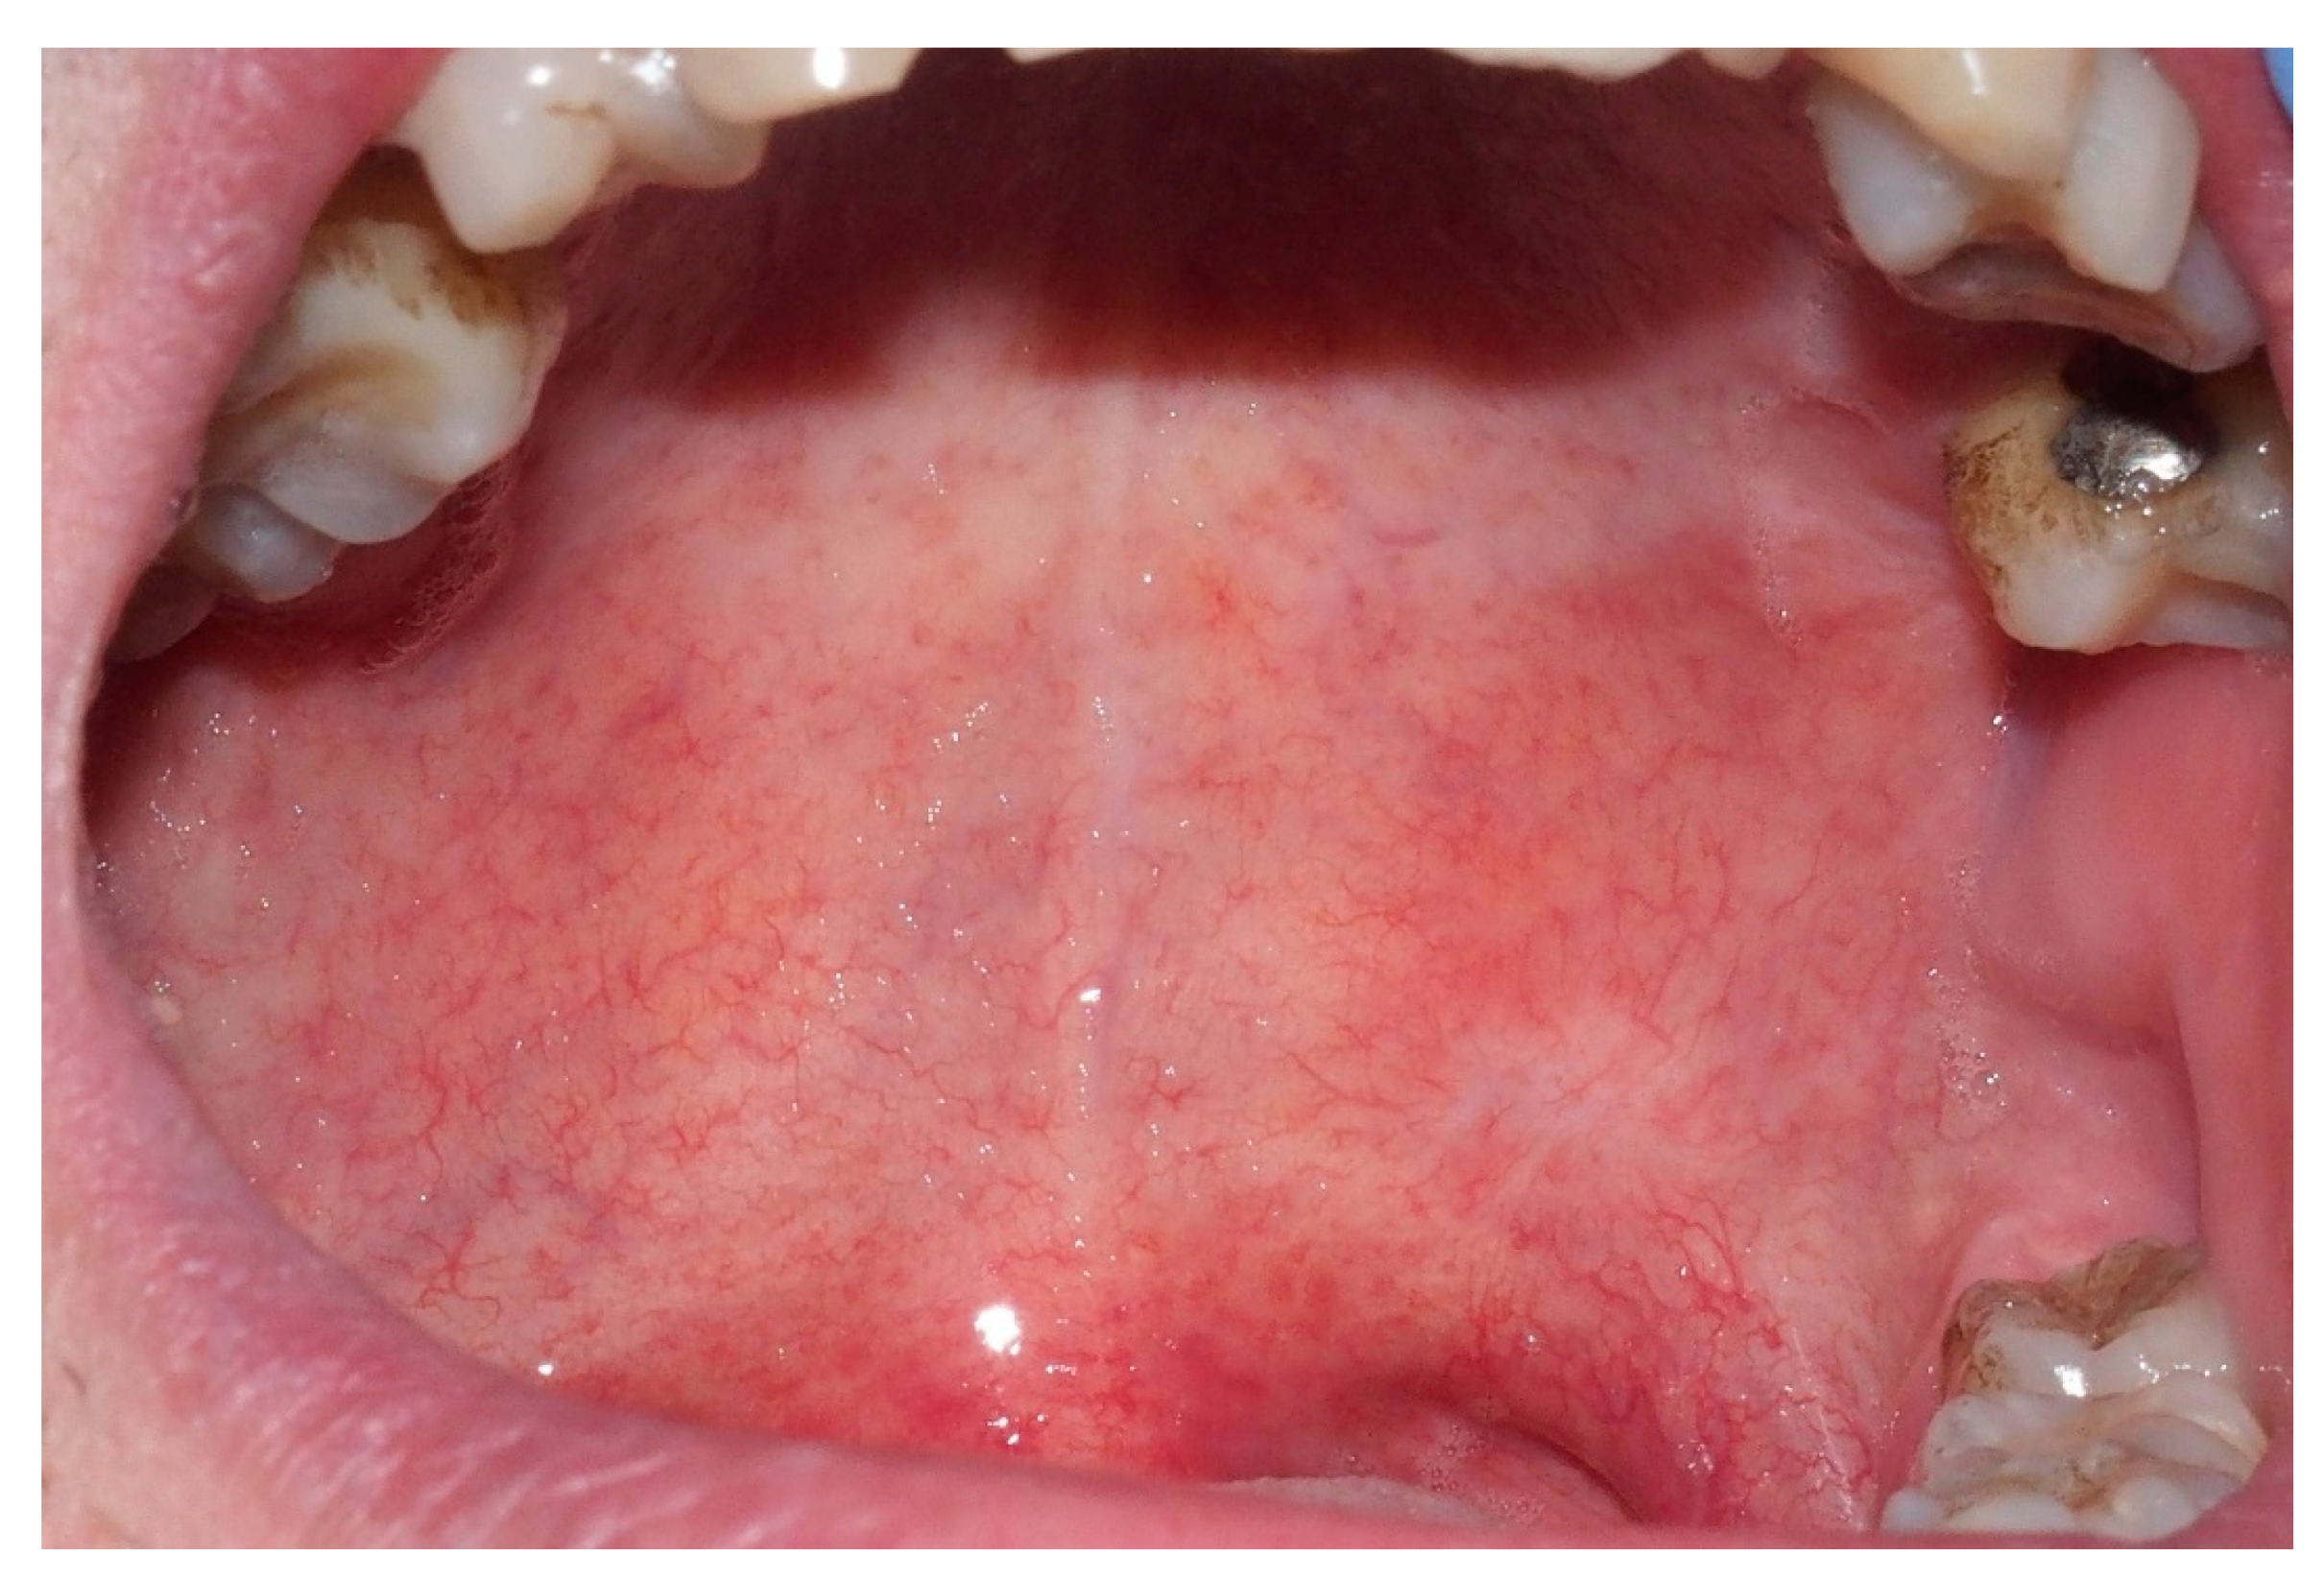

2. Case Report

3. Discussion